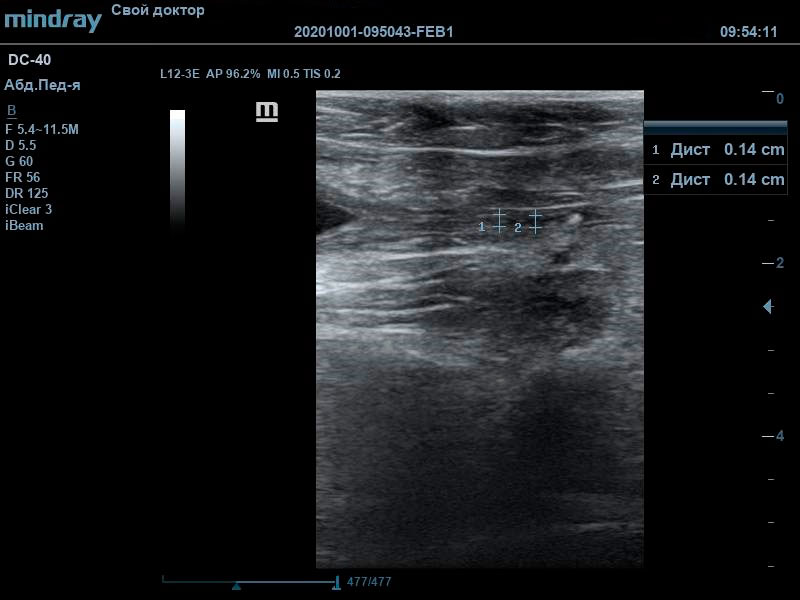

При проведении ультразвуковой диагностики врачом были выявлены крайняя степень наполнения мочевого пузыря, обильный пристеночный осадок с акустической тенью. Мочевой треугольник и проксимальная часть уретры также были расширены, в данной локации также визуализировались сформированные конкременты, размером до 3 мм. В почках определялись признаки билатеральной пиелоэктазии на фоне нарушения оттока мочи из мочевого пузыря.